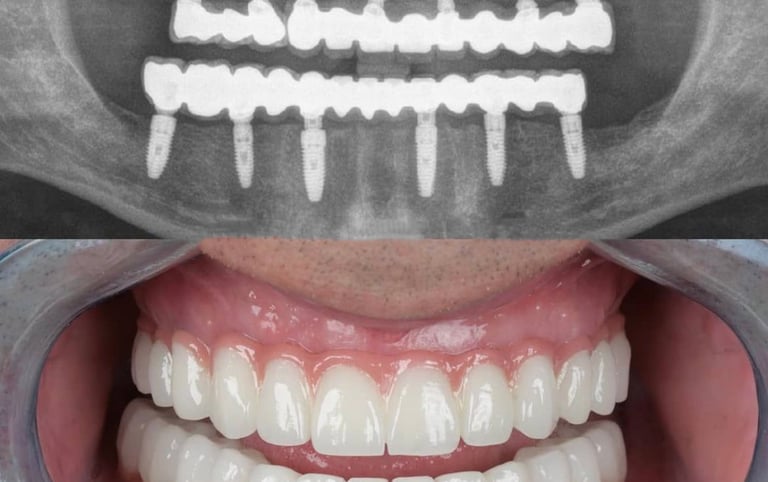

Implants

If you are missing one or more teeth, dental implants are the most reliable and natural-looking solution.

Implants act as artificial tooth roots, providing a stable foundation for crowns, bridges, or dentures. Benefits include:

• Permanent and durable replacement

• Natural function and aesthetics

• Preservation of jawbone and facial structure

At Dr. Teeth, we use advanced implantology techniques for safe, effective, and long-lasting results.